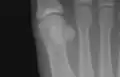

Sesamoid bones at the distal end of the first metatarsal.